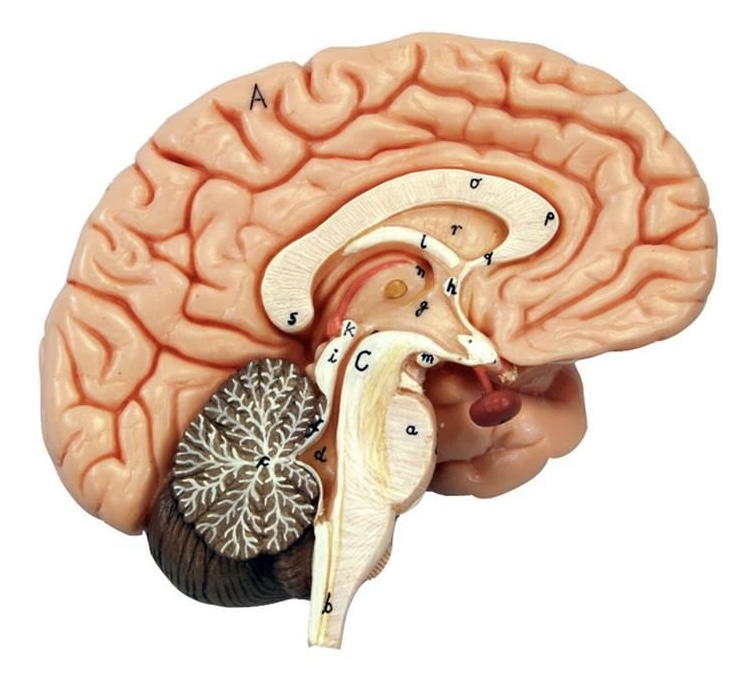

What is D?

lateral ventricle

Imagine thin membrane separating the 2 lateral ventricles

septum pellucidum

What is C?

3rd ventricle

What is B?

cerebral aqueduct

What is A?

4th ventricle

What is below A at the very end?

central canal (spinal cord)

What is C?

midbrain

tectum (corpora quadrigemina): superior colliculus

tectum (corpora quadrigemina): inferior colliculus

What is a?

pons

medulla oblongata

intermediate mass of thalamus

hypothalamus

What is the pink bulb?

pineal gland

corpus callosum

fornix

What is A?

cerebral cortex

cerebral tracts

cerebral hemispheres

longitudinal fissure

What are these ridges?

gyri

What are these shallow grooves?

sulci

Divides parietal from frontal lobe

central sulcus

precentral gyrus

postcentral gyrus